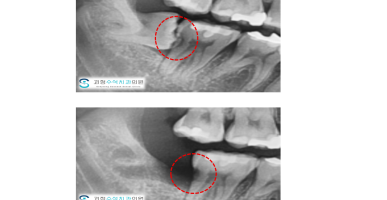

사랑니를 뽑아야하는 이유

보이시나요? 사랑니를 발치해보니 오랜기간 사용해야하는 큰 어금니가 사랑니의 영향으로 흡수가 되었어요....